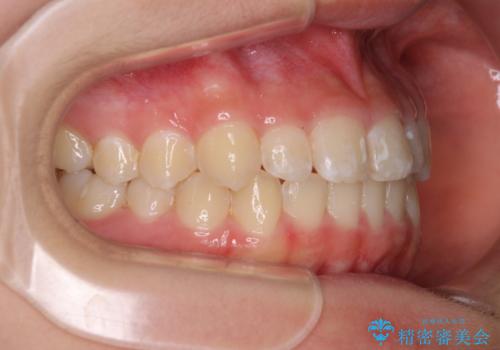

遠方から新幹線で通院 急速拡大装置とインビザラインによる矯正治療

- 小児矯正の頃から診察を行っている患者様です。

上顎骨の幅が下顎骨よりも小さいので、拡大装置により骨幅を広げて上下関係を改善し、その後インビザラインにて歯並びを整えることとしました。

上下の骨幅を改善したことで、スムーズに歯列矯正を行うことができました。

インビザライン治療開始直後に遠方に引っ越しをされたため、通院間隔が長くなり、治療期間が長くなりましたが、しっかりと治療を行うことができました。